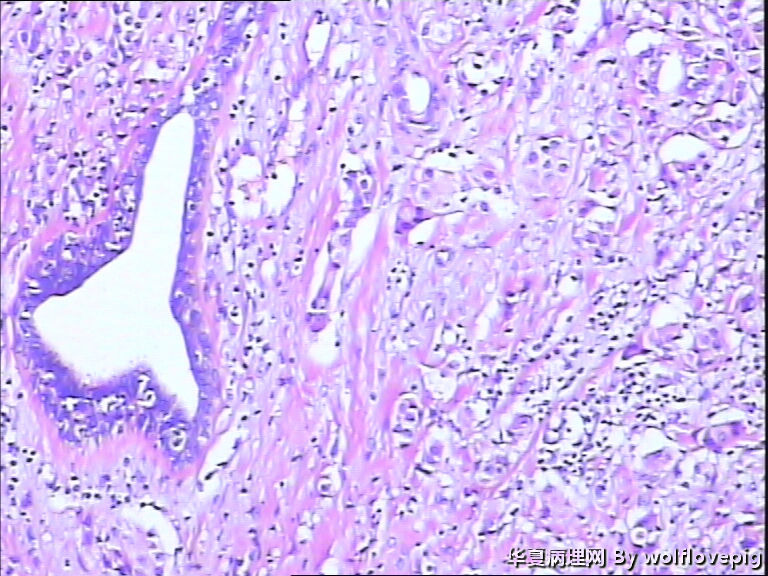

B3937求助!乳腺包块。

女,60y,发现右乳包块6+月。

灰白不整形组织一块:3*2*1.5cm,切面有一灰白区域,边界欠清,质韧。

• 求助!乳腺包块。图1

图1

• 求助!乳腺包块。图2

图2

• 求助!乳腺包块。图3

图3

• 求助!乳腺包块。图4

图4

标签:乳腺浸润性癌

浸润性癌。

浸润性导管癌,最好标记肌上皮。

浸润性导管癌

浸润性导管癌,分化差,除外混合癌(导管癌+小叶癌),免疫组化证实。(本例图像很多,局部炎症反应重,瘤细胞还成合体样无腺管形成似髓样癌,局部似炎性乳癌,局部似小叶癌,呵呵)